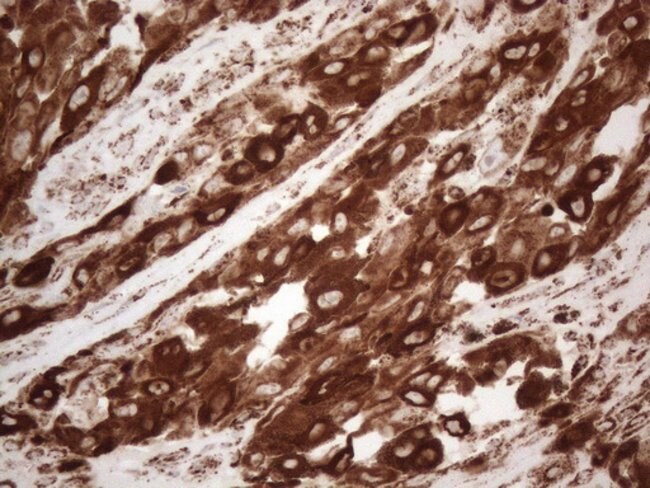

MLANA Monoclonal Antibody (OTI2E7), TrueMAB™, OriGene

MART-1 (Melanoma Antigen Recognized by T cells 1) or Melan-Ais a newly identified melanocyte differentiation antigen recognized by autologous cytotoxic T lymphocytes. Seven other melanoma associated antigens recognized by autologous cytotoxic T cells include MAGE-1, MAGE-3, tyrosinase, gp100, gp75, BAGE-1, and GAGE-1. Subcellular fractionation shows that MART-1 is present in melanosomes and endoplasmic reticulum.Specifications

Immunohistochemistry (Paraffin), Western Blot | |